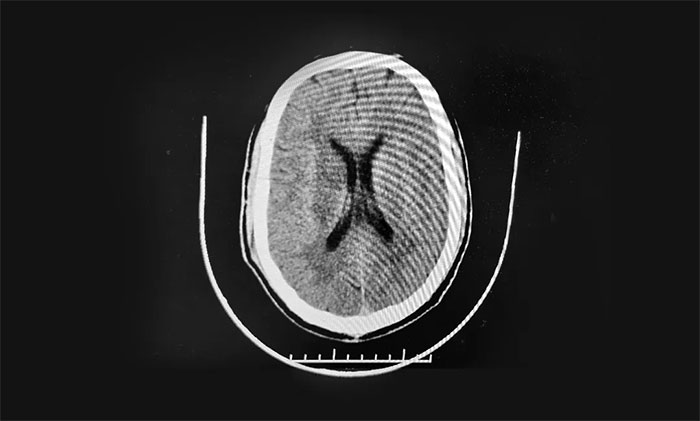

47歲男子突發(fā)腦梗 半身偏癱

47歲的王先生是個“老煙槍”,每天至少一包煙,而且他還有糖尿病、高血壓病史。10月2日凌晨,晨起時突然出現(xiàn)左側(cè)肢體活動受限,上肢近端不能抬起,手不能持物,左下肢不能行走,而且語言不清。慌亂之間,家人當即撥打120送醫(yī)急診。經(jīng)頭顱CT檢查:右側(cè)額葉腦梗死,入院后給予一系列藥物口服治療8天,效果不佳,并且王先生感覺左側(cè)肢體活動不利較前加重。為求進一步治療,王先生一家到上海求醫(yī),后慕名轉(zhuǎn)入上海藍十字腦科醫(yī)院神經(jīng)內(nèi)科,由張靜波主任主診。

▲ 右側(cè)基底節(jié)腦梗死

患者既往有糖尿病病史7年,血糖控制在13毫摩爾每升。高血壓3級極高危,收縮壓最高180毫米汞柱,舒張壓最高100毫米汞柱。

入院時,患者左上肢近端肌力2級,左上肢遠端肌力0級,左下肢近端肌力2級,左側(cè)下肢遠端肌力0級,肌張力正常。NIHSS評分11分。

頭顱CTA示:左側(cè)頸內(nèi)動脈C4-5段、右側(cè)頸內(nèi)動脈C5段鈣化斑塊形成。右側(cè)大腦中動脈M1段及左側(cè)大腦中動脈M2段重度狹窄。頭顱CTP示:兩側(cè)幕上腦微循環(huán)不良:慢期缺血、血容量CBV下降為主(右基底節(jié)區(qū)較顯)。

綜合相關(guān)檢查,患者確診:右側(cè)基底節(jié)區(qū)梗死。